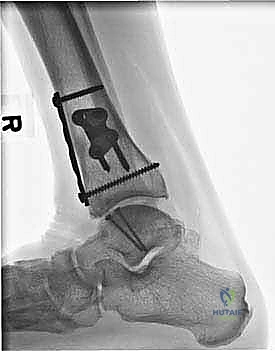

- التصوير بالأشعة السينية (X-rays): الخطوة الأولى لاستبعاد الكسور الكبيرة وتقييم المحاذاة العامة للعظام. قد تظهر الأشعة السينية الآفات الكبيرة، لكنها غالباً ما تفشل في إظهار التلف الغضروفي المبكر.

- التصوير المقطعي المحوسب (CT Scan): ضروري جداً للآفات الكبيرة. يوفر الـ CT صورة ثلاثية الأبعاد للعظم، مما يساعد الجراح في التخطيط الدقيق لعملية قطع العظم وحجم الطعم المطلوب زراعته.